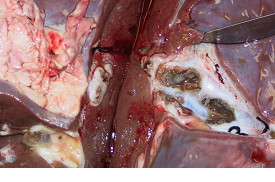

Fig 4: Blackleg affecting one hind leg - note the extensive swelling and black (necrotic) muscle. The unaffected hind leg is shown below (fig 5).

Affected cattle are often found dead. More typically, affected cattle are very dull and depressed, do not feed and have a very high rectal temperature (>41.0°). Involvement of one limb results in sudden onset severe lameness. There is obvious muscle necrosis at postmortem examination.

Fig 5: Unaffected hind leg - compare with affected leg above (fig 4).